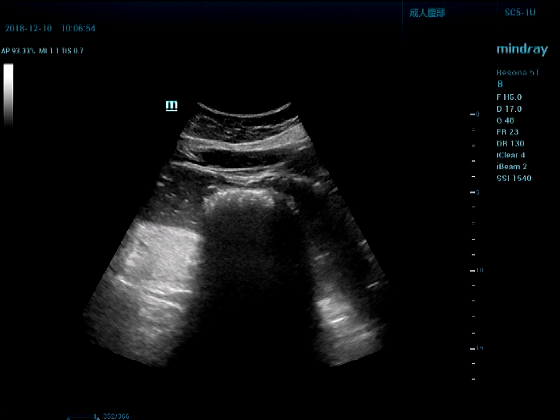

病例一:女,53岁,胃部不适一周来诊

超声可见:胃腔内见一小鸡蛋大强回声团块,后方伴强声影,位置活动。

问及病史吃山楂,柿子。

超声提示:结合临床考虑胃结石,治疗后复查